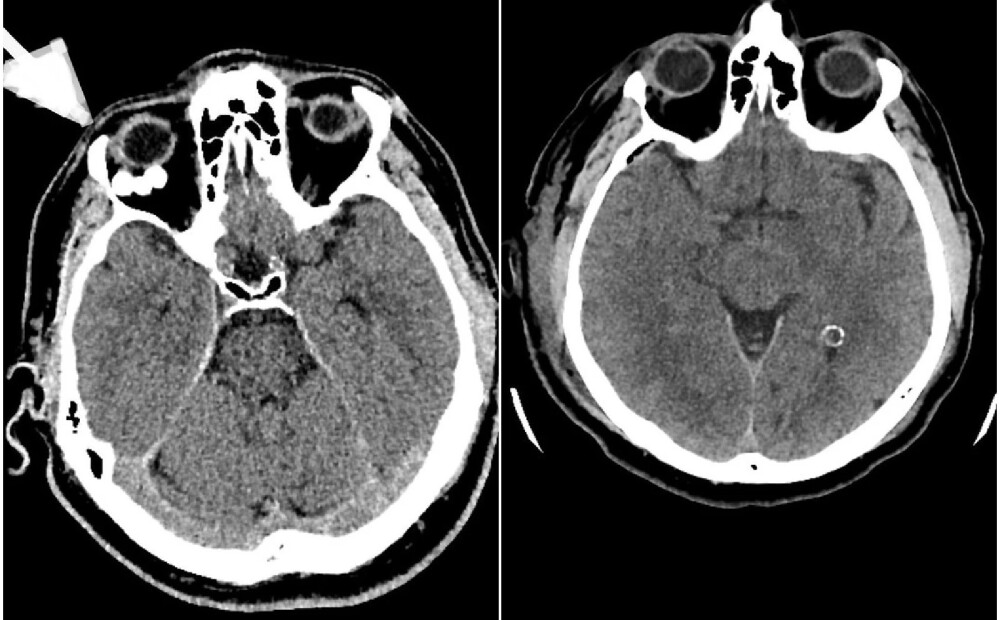

Paula Stradiņa Klīniskās universitātes slimnīcas (PSKUS) Neiroķirurģijas klīnikā 7.janvārī veikta unikāla un ārkārtīgi reta operācija pacientam ar neparastu patoloģiju – blīvu, kalcinētu veidojumu acs dobumā aiz acs ābola, ziņo PSKUS sabiedrisko attiecību daļas vadītāja Vineta Kļaviņa.